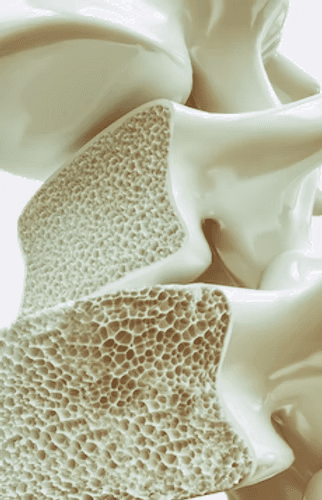

The result of extensive Italian research, Limfa® Therapy is a state-of-the-art, regenerative medical device for non-invasive cellular stimulation. Using ultra-weak magneto-electric fields, Limfa® Therapy is able to accelerate cellular self-repair with a scientifically proven average effectiveness of 80%. Regeon Bone and Body Institute is the first FDA-cleared therapeutic facility in the US to use this groundbreaking technology, allowing us to help our clients with pain management, inflammation reduction, and bone, cartilage and connective tissue repair.

Strength training is a long-term cornerstone for recovery, injury prevention, and healthy aging because it builds the muscular support your joints and connective tissues rely on every day. Progressively building key areas like the hips, knees, back, core, and shoulders, improves balance, posture, and movement control, helping to reduce strain on vulnerable joints and lowering the risk of recurring injuries. A well-designed strength program also increases bone density, enhances tendon resilience, and supports healthy biomechanics, making everyday activities and athletic performance safer and more efficient.

A balanced routine is essential for long-term recovery, maintenance, and preventing future injury or further degeneration because the body adapts to what you practice regularly. Preventative Limfa® Therapy and supportive strength training help protect your joints, maintain healthy movement patterns, and keep bones, muscles, and connective tissues resilient over time, while a sustainable wellness plan helps you achieve a balanced and vibrant life. When paired with smart lifestyle fundamentals like quality sleep, stress management, and proper hydration, these principles of health and well-being will have you not only living longer, but living longer better, thriving well into your adult years.